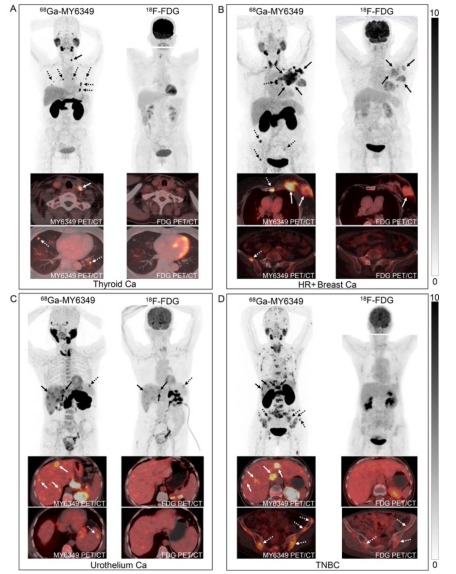

68Ga-MY6349與18F-FDG PET/CT在不同腫瘤中的臨床診斷效能

由于68Ga-MY6349在許多上皮起源腫瘤中的攝取顯著高于正常器官,我們進(jìn)一步分析了68Ga-MY6349 PET/CT對(duì)不同類(lèi)型腫瘤的診斷效果,并將其與臨床常用的18F-FDG PET/CT進(jìn)行了對(duì)比。在原發(fā)性腫瘤的診斷中,68Ga-MY6349與18F-FDG在鼻咽癌、HR+乳腺癌、HER2+乳腺癌、三陰性乳腺癌、食管癌、非小細(xì)胞肺癌、婦科腫瘤和前列腺癌的顯像劑攝取值無(wú)統(tǒng)計(jì)學(xué)差異。然而,在HR+乳腺癌中,68Ga-MY6349 PET/CT的TBR顯著優(yōu)于18F-FDG PET/CT(11.0 vs. 4.0,P = 0.002),檢測(cè)到的乳腺腫瘤病灶數(shù)目更多(14 vs. 12)。在HER2+乳腺癌、尿路上皮癌和前列腺癌中也觀察到類(lèi)似結(jié)果,68Ga-MY6349 PET/CT顯示出更高的TBR并檢測(cè)到更多腫瘤病灶。

在復(fù)發(fā)和轉(zhuǎn)移性腫瘤的檢測(cè)方面,68Ga-MY6349 PET/CT在甲狀腺乳頭狀癌、前列腺癌和HR+乳腺癌中的SUVmax和TBR均高于18F-FDG PET/CT,因此能夠識(shí)別出更多的轉(zhuǎn)移病灶,特別是在檢測(cè)淋巴結(jié)轉(zhuǎn)移(如甲狀腺乳頭狀癌)、骨轉(zhuǎn)移(如HR+乳腺癌)和肝轉(zhuǎn)移(如尿路上皮癌)方面表現(xiàn)突出。代表性病例見(jiàn)圖6A-C。在三陰性乳腺癌患者的68Ga-MY6349 PET/CT中,盡管TNBC病灶對(duì)68Ga-MY6349的SUVmax與18F-FDG相似,但TBR顯著更高,使其能夠檢測(cè)到更多隱匿性或微小轉(zhuǎn)移病灶(135 vs. 123),尤其是在肝臟和骨轉(zhuǎn)移的檢測(cè)上(圖6D)。相反,18F-FDG PET/CT在鼻咽癌、HER2+乳腺癌、食管癌、胰腺癌和婦科腫瘤中具有更高的SUVmax,并檢測(cè)到更多轉(zhuǎn)移病灶。上述結(jié)果顯示,68Ga-MY6349 PET/CT在甲狀腺癌、前列腺癌、乳腺癌、尿路上皮癌等腫瘤的診斷中具有良好的臨床應(yīng)用前景,有望為現(xiàn)有的影像技術(shù)提供有效補(bǔ)充。

圖 6. 不同腫瘤患者18F-FDG和68Ga-MY6349的代表性PET/CT圖像。(A)一例68歲女性甲狀腺乳頭狀癌,一年前接受手術(shù)切除,PET/CT檢測(cè)腫瘤復(fù)發(fā)。68Ga-MY6349 PET/CT顯示頸部淋巴結(jié)(實(shí)箭頭)和肺部轉(zhuǎn)移(虛箭頭)高度攝取,而18F-FDG PET/CT為假陰性。(B)一例74歲女性激素受體陽(yáng)性乳腺癌患者,接受PET/CT進(jìn)行腫瘤分期。68Ga-MY6349 PET/CT在原發(fā)腫瘤(實(shí)箭頭)、淋巴結(jié)和骨轉(zhuǎn)移(虛箭頭)中顯示出較18F-FDG PET/CT更高的示蹤劑攝取。此外,18F-FDG PET/CT在骨轉(zhuǎn)移中為假陰性。(C)一例63歲男性尿路上皮癌(膀胱癌)患者接受PET/CT進(jìn)行分期。68Ga-MY6349 PET/CT在原發(fā)和轉(zhuǎn)移病灶中顯示了較18F-FDG PET/CT更高的示蹤劑攝取和更好的圖像對(duì)比,特別是肝臟轉(zhuǎn)移(實(shí)箭頭)和脾轉(zhuǎn)移(虛箭頭)。(D)一例65歲女性三陰性乳腺癌患者,多線治療后進(jìn)展,接受PET/CT進(jìn)行再分期。68Ga-MY6349 PET/CT在淋巴結(jié)、肝臟(實(shí)箭頭)和廣泛骨轉(zhuǎn)移(虛箭頭)中顯示出明顯的示蹤劑攝取,而18F-FDG PET/CT在大多數(shù)轉(zhuǎn)移病灶中顯示低至中等攝取。